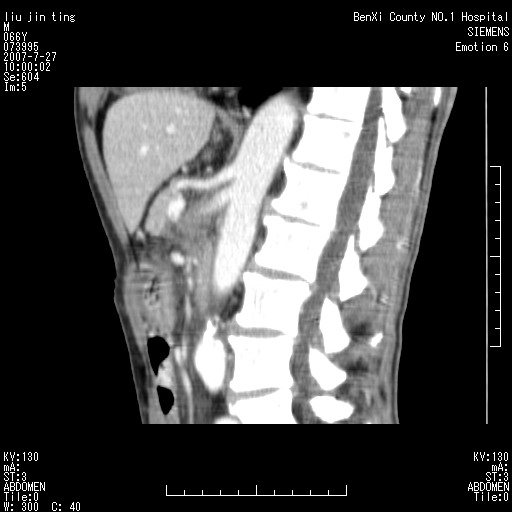

腹痛,背痛,无恶心呕吐,不黄,彩超示胰腺钩癌,ct扫描病灶平扫30-40hu,增强后动脉期40--60hu,静脉期50-68hu,真的是钩突上的么?您要试一试么?

动脉期

静脉期